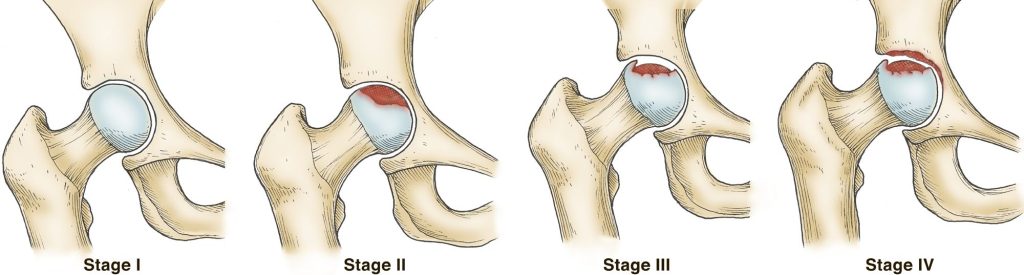

The four stages of osteonecrosis. The disease can progress from a normal, healthy hip (Stage I) to the collapse of the femoral head and severe osteoarthritis (Stage IV).

Reproduced and adapted from Beaule PE, Amstutz, HC: Management of ficat stage III and IV osteonecrosis of the hip. J Amer Acad Orthop Surg 2004; 12: 96-105.